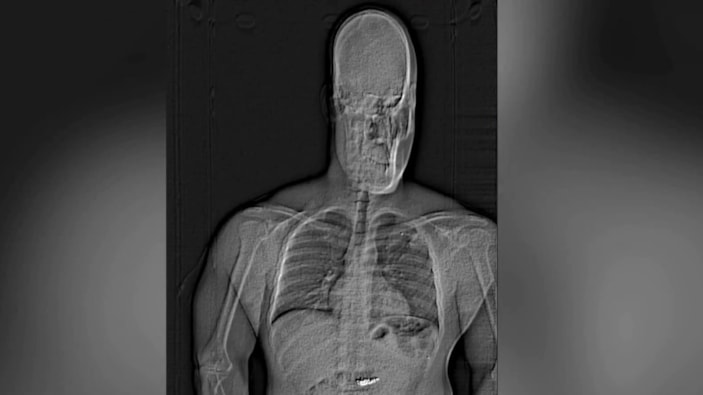

Gilder'ın röntgen muayenesinde çaldığı küpelerin midesinde olduğunun tespit edildiği kaydedilen açıklamada, hırsızın günlerce hastanede gözetim altında tutulduğu vurgulandı.